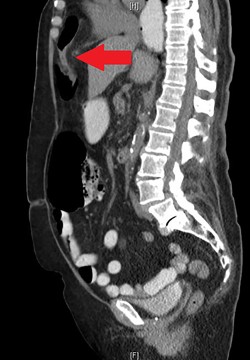

During the hospitalization, initial cardiac workup with 12-lead electrocardiogram and serial troponins was negative. The patient’s oncologic medications were held without improvement of the pain as well as to prevent leukopenia and neutropenia, if surgery was indicated. Palliative care was unable to achieve adequate pain control with oral and IV medications, and the patient did not want to pursue hospice care. Surgical consultation was obtained, and further evaluation with a CT scan of the chest, abdomen and pelvis with oral and IV contrast demonstrated an anteromedial diaphragmatic defect through which a prominent amount of mesenteric fat and a portion of the colon herniated representing a Morgagni hernia (Figs. 1–4). An increase in the size of the previously known PEH as well as the Morgagni hernia was noted. Due to continued chest pain unrelieved by opioids, a joint decision was made between surgeon, oncologist and the patient to proceed with surgery. She underwent successful robotic laparoscopic repair of the Morgagni hernia and PEH with dulex mesh for reinforcement. Her chest pain subsequently resolved. The patient gradually tolerated oral feeds and was eventually discharged in stable condition.

The CT abdomen and pelvis with oral contrast from 2015 pictured above led to an initial diagnosis of a Morgagni hernia, identified by the red arrow.